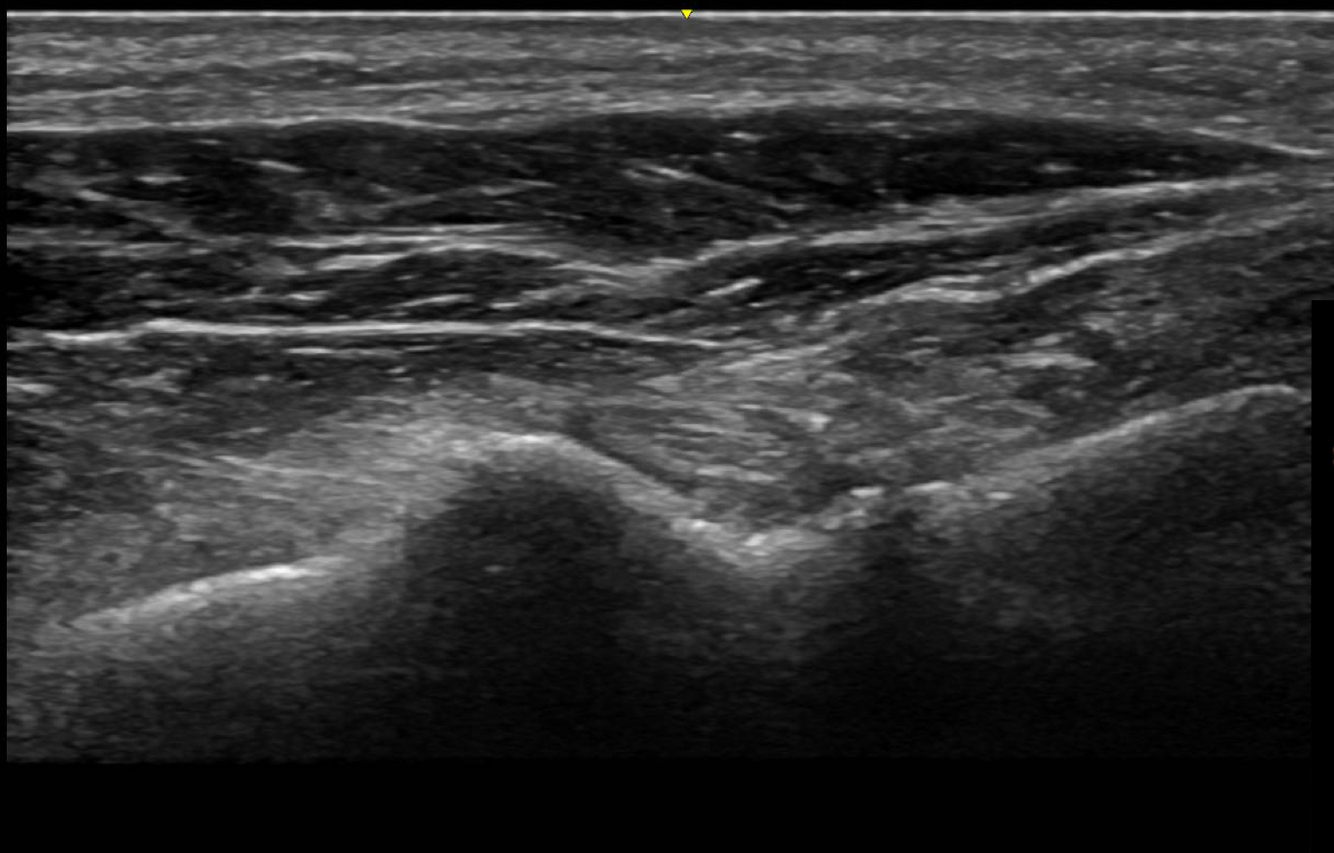

Quoi la pathologie ici?

Kyste ganglionnaire intra-neural (où il y a des petites étoiles